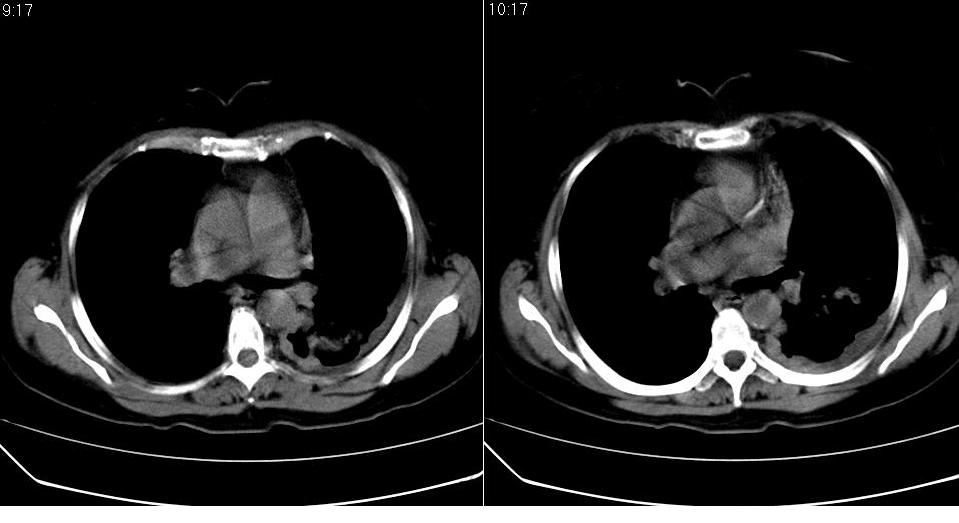

女 59岁,胸背疼,不咳嗽,不咳痰,不发热。

1)考虑左肺下叶背段周围型肺癌并左肺下叶及左侧胸膜转移。2)左侧胸腔积液。3)左冠状动脉钙化。

1)考虑左肺下叶背段周围型肺癌(腺癌可能性大)并左肺下叶及左侧胸膜转移。2)左侧胸腔积液。3)左冠状动脉钙化。